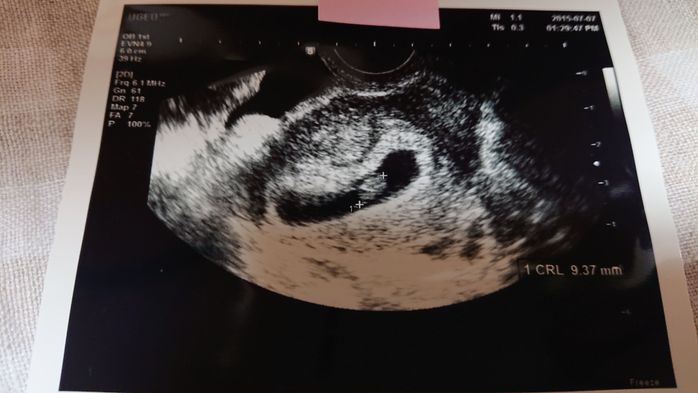

《妊娠7週目のエコー写真》

妊娠7週目の健診日には、午前中に夫と一緒に市役所へ婚姻届けを提出し、母子手帳も発行してもらいました。夫は車酔いをして具合が悪くなってしまったので、健診の時は夫には留守番をしてもらい、もらいたてホヤホヤの母子手帳を手に、1人でドキドキしながら産婦人科へ行きました。すると、胎嚢の中に赤ちゃんの姿が…!「やっと会えたね~」と、嬉しすぎて食い入るように見ていたエコーの画面。「もっともっと長く見ていたい」と切に願ったほど感激しました。そして、この日は同時に心拍も確認でき、心臓も元気に動いていました。2枚目のエコー写真の右側半分が、心拍を確認できた証拠です。医師からは「小さすぎて予定日はまだ決められないな~。でも、3月上旬ぐらいになるかな~」と伝えられ、予定日確定は次回持ち越しに。夫は「成長遅いんじゃない?」と心配そうにしていました。翌日には、私たちの結婚式が控えていました。その前に赤ちゃんの姿を見つけることができたおかげで、遠方の両親にも直接妊娠報告することができて嬉しかったです。